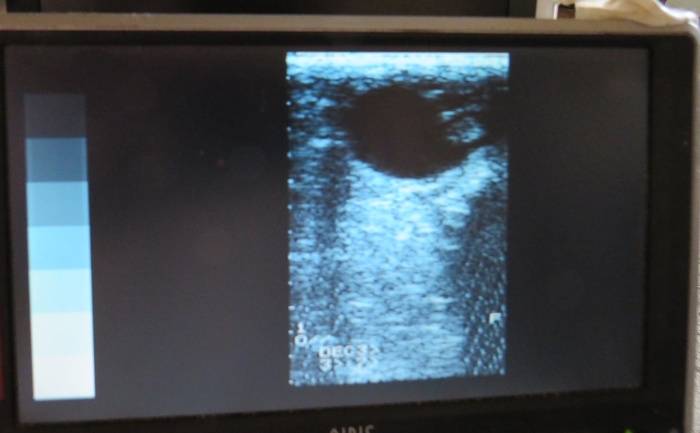

La grossesse de Diadème se poursuit très bien.

Échographie d'aujourd'hui: Le poulain est en haut à droite dans son “oeuf” situé en haut à droite de l'écran.

A comparer avec la semaine dernière:

Térence a fait un film. Dès que possible je vous le mets pour voir les battements cardiaques….